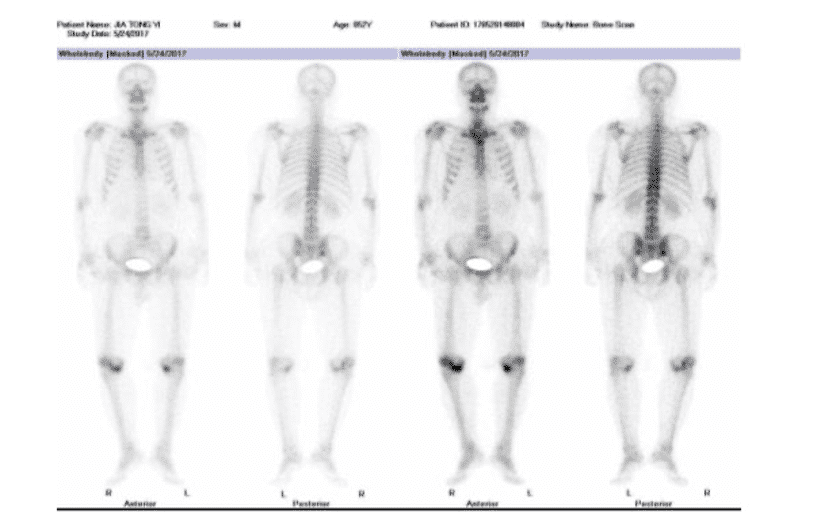

胸9-腰1椎体:右骶骼关节轻度浓聚灶,建议定期复查。双膝关书浓聚灶,请结合临床考虑。